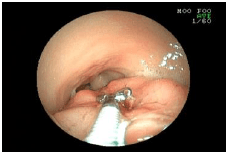

1. 胃の中の種を取り出した例

![]() |

モモの種を飲み込んでしまった犬の胃の内視鏡画像です。 胃の中に種が見えます。(矢印) |

内視鏡の先端から、種をつかむための器具(矢印)を伸ばしています。 |